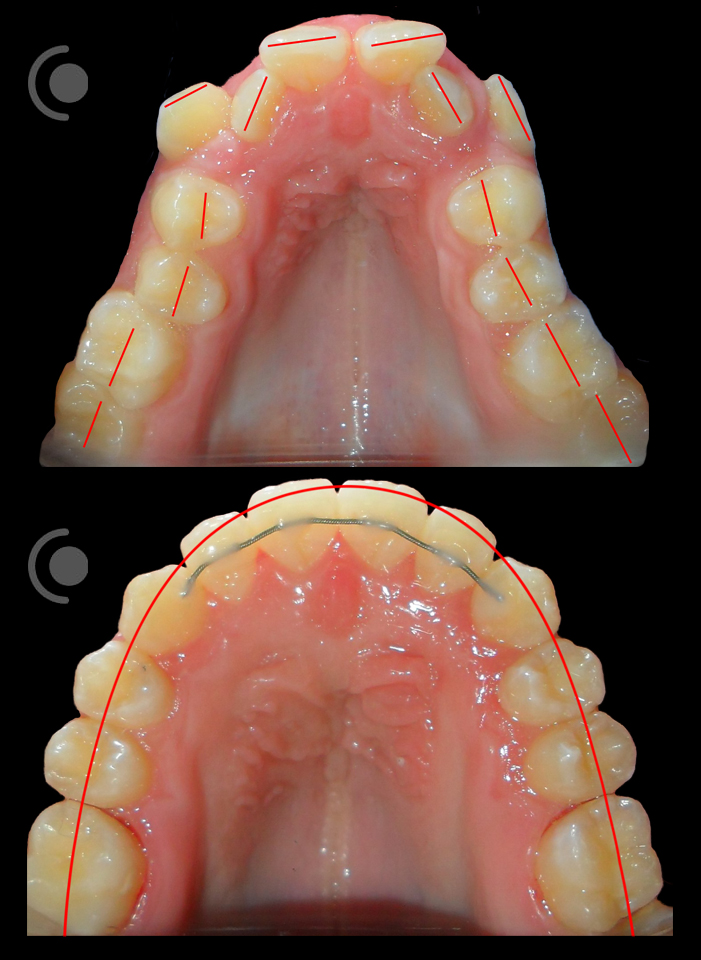

O našoj kvaliteti najbolje govore naši rezultati!

Centar za ortodonciju Petra Džapo